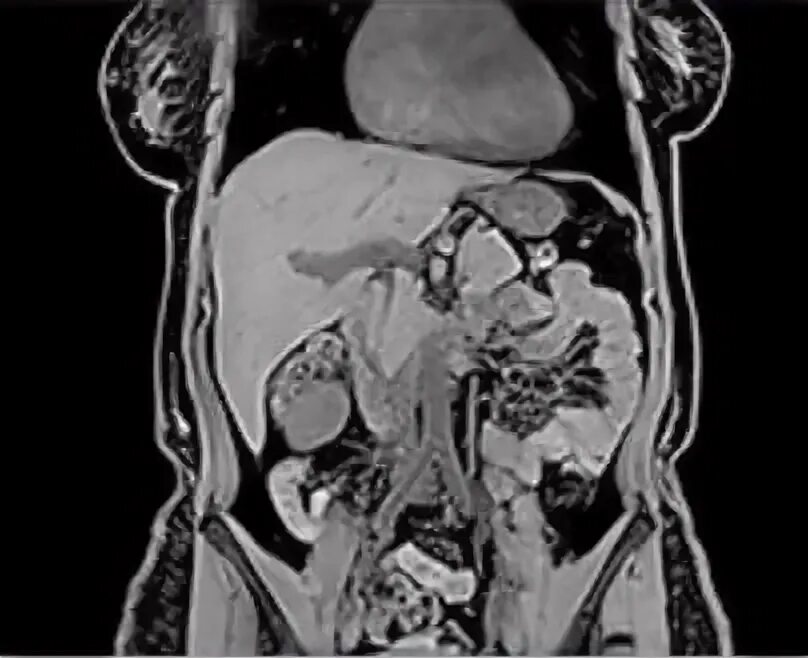

Кишечник обследование мрт